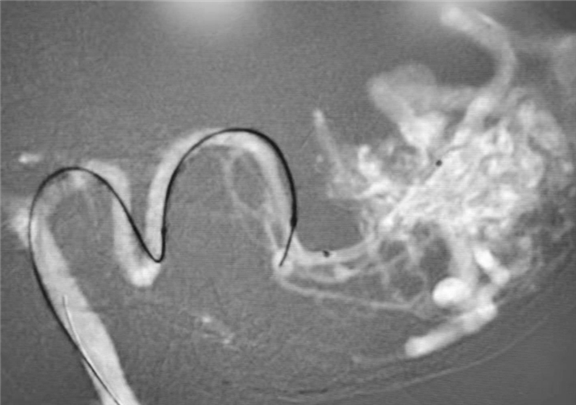

术中造影精确显示脑血管畸形合并颅内动脉瘤

用微弹簧圈栓塞颅内动脉瘤,用ONXY胶栓塞血管畸形团,注胶过程中可以充分显示畸形血管,准确判断胶的走行,有利于保护周围正常血管,有效减少过度栓塞导致脑梗死等并发症